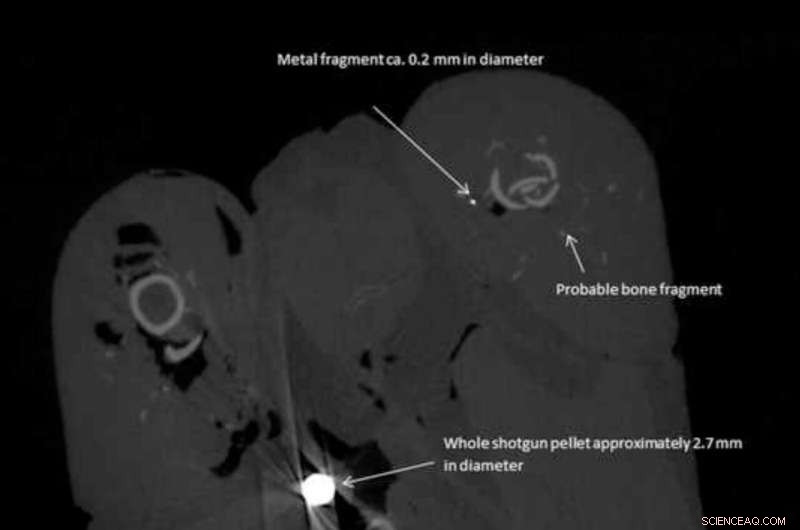

This shows a whole shotgun pellet, a small metal fragment and a probable bone fragment. Note the obvious artifact effect around the shotgun pellet. Credit: University of Cambridge

The researchers used a high-resolution CT (computerized tomography) scanner to locate the lead fragments in the pheasant meat in three dimensions, and measure their size and weight. The meat was then dissolved, allowing the larger fragments to be extracted and analyzed further to confirm they were lead.

An average of 3.5 lead pellets and 39 lead fragments of less than 1mm wide were detected per pheasant. The smallest fragments were 0.07mm wide—at the limit of resolution for the CT scanner for specimens of this size—and the researchers say it is likely that even smaller fragments were also present.

The lead pieces were widely distributed within the birds' tissues and some of the small fragments were over 50mm from the nearest lead shot pellet.